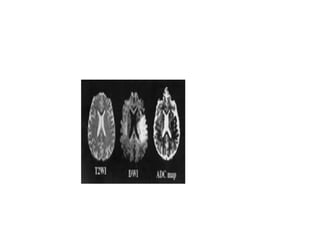

Diffusion Weighted Imaging (DWI)

• DWI is the most sensitive sequence for

stroke imaging.

DWI is sensitive to restriction of Brownian

motion of extracellular water due to

imbalance caused by cytotoxic edema.

Normally water protons have the ability to

diffuse extracellularly and loose signal.

High intensity on DWI indicates restriction

of the ability of water protons to diffuse

extracellularly.

This is why DWI is called 'the stroke

sequence'

MRI VS TIME

• ADC will be of low signal intensity with a

maximum at 24 hours and then will

increase in signal intensity and finally

becomes bright in the chronic stage.